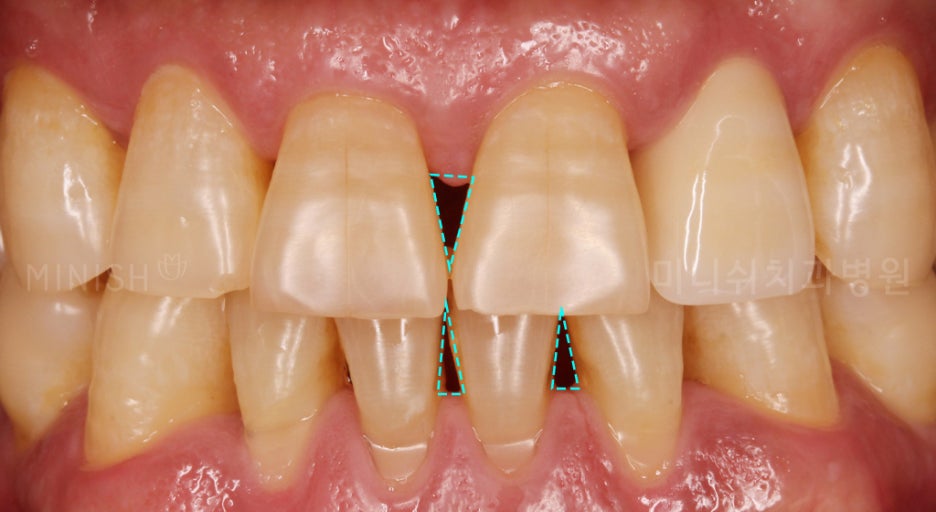

구강 건강을 회복하기 위해서는 세균의 번식을 막아야하는데, 이때 필요한 것이 스케일링입니다. 치은염과 같은 경미한 증상은 대부분 묵은 치석과 치태를 제거하는 스케일링만으로 효과를 볼 수 있습니다. 팽팽하게 부어있던 붓기가 빠지는 것이 건강을 회복했다는 증거인데요. 비로소 사라진 치은이 적나라하게 드러나기 때문에 블랙트라이앵글, 시린이 등의 문제가 나타나기도 합니다.

잇몸염증 치료 후 드러난 치근, 블랙트라이앵글